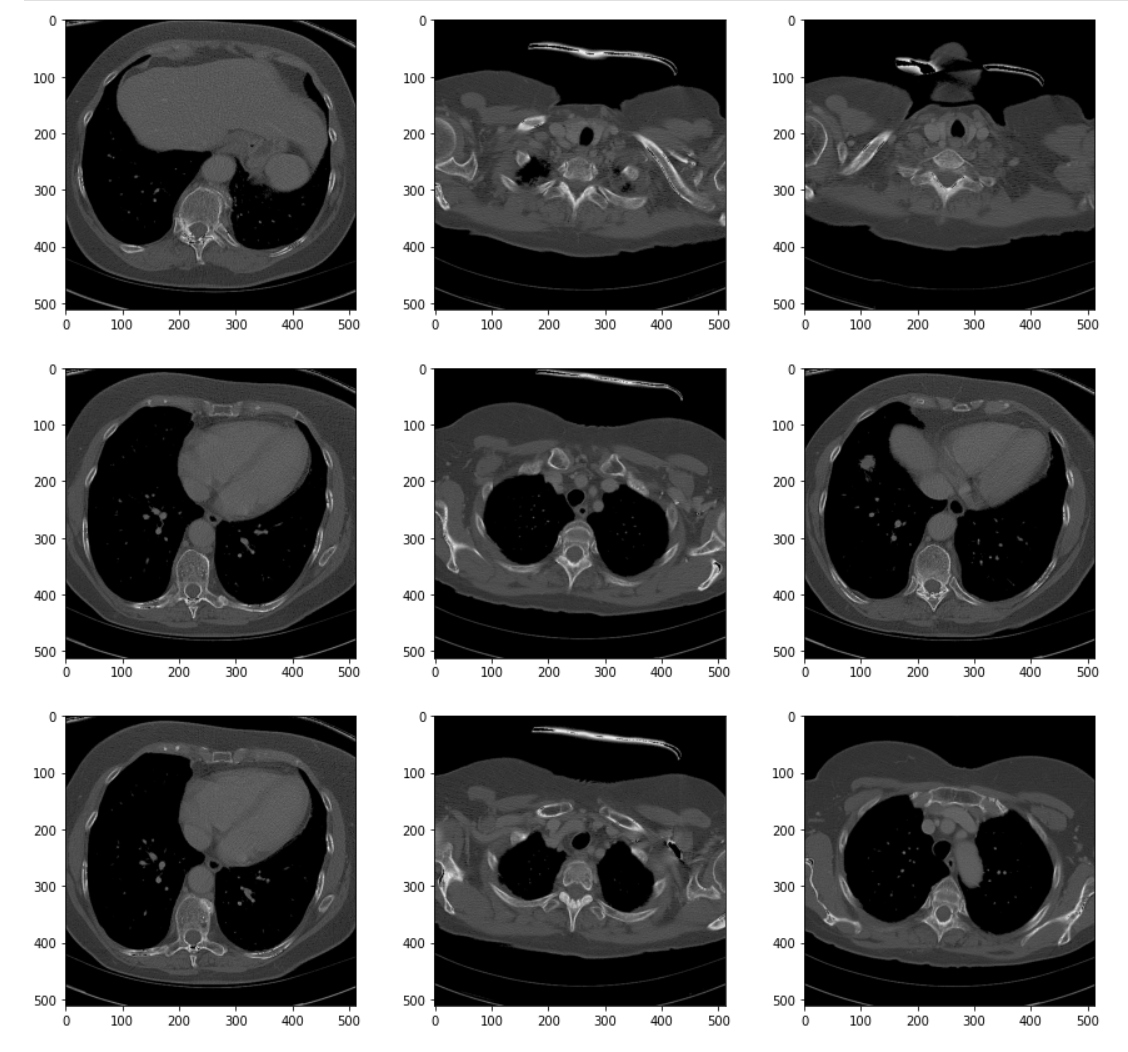

To see the results of the transformation, we can visualize the series using the same helper from earlier.

# Visualize the resulting transformation plt.pyplot.figure(figsize=(15,35)) display_series(ct_idata1)

The processed images show better differentiation between the tissue types. It's easier to distinguish one type of soft tissue -- skin, fat, and muscle (for example) -- from others. The effects of the transforms become more obvious if we visualize the histogram of the transformed volume.

# Visualize the new histogram plt.pyplot.figure(figsize=(8, 8)) sns.distplot(ct_idata1.flatten())

While this is a good start, even with the processing we've done the difference between tissues is still subtle. We could further stretch the contrast and apply other types of filters and max to further suppress artifact and noise. Nevertheless, we've taken a good first step.